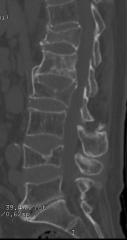

70岁的梁奶奶,家人说老人家因提重物导致腰背疼痛,正因疫情期间,在家休息仍无缓解,因疼痛无法正常生活,迫于为梁奶奶解除痛苦,居家7天后家人带其来到我院就诊,张昊主任医师阅读了相关影像学资料,经过团队的讨论,首先明确诊断为 “1.胸12、腰1椎体压缩性骨折 2.重度骨质疏松症”。针对老年人骨质疏松导致椎体压缩性骨折的治疗,把相关治疗方案以及相应的风险等事宜详细告知家属,最终采用经皮穿刺椎体后凸成形术为梁奶奶进行手术,术后疼痛明显缓解,效果非常满意,第二天顺利出院。

术后影像